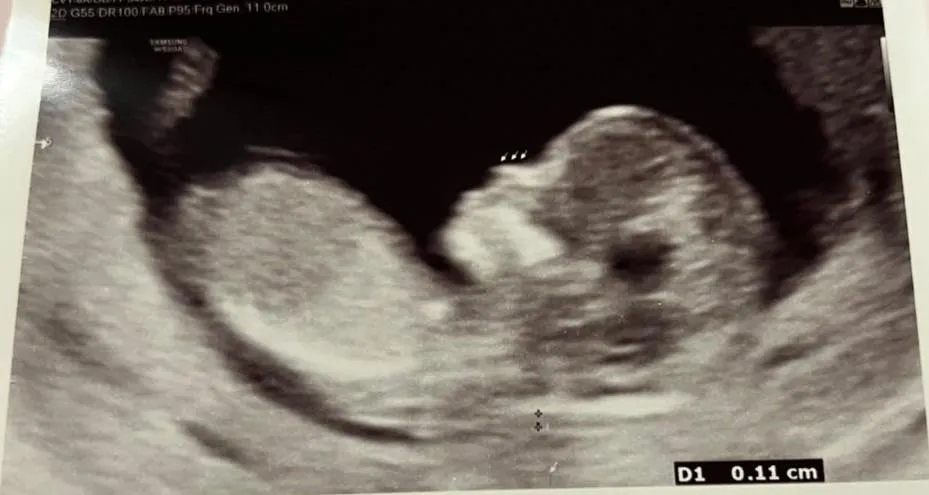

凌涛今发文和大家分享喜讯,「上天给我的幸运,8年后再迎接第二个宝贝孩子」,透露今天是他36岁生日,这几个月除了塞满的工作外,最期待的就是每一次的产检,看看小朋友进度,很高兴他健健康康。